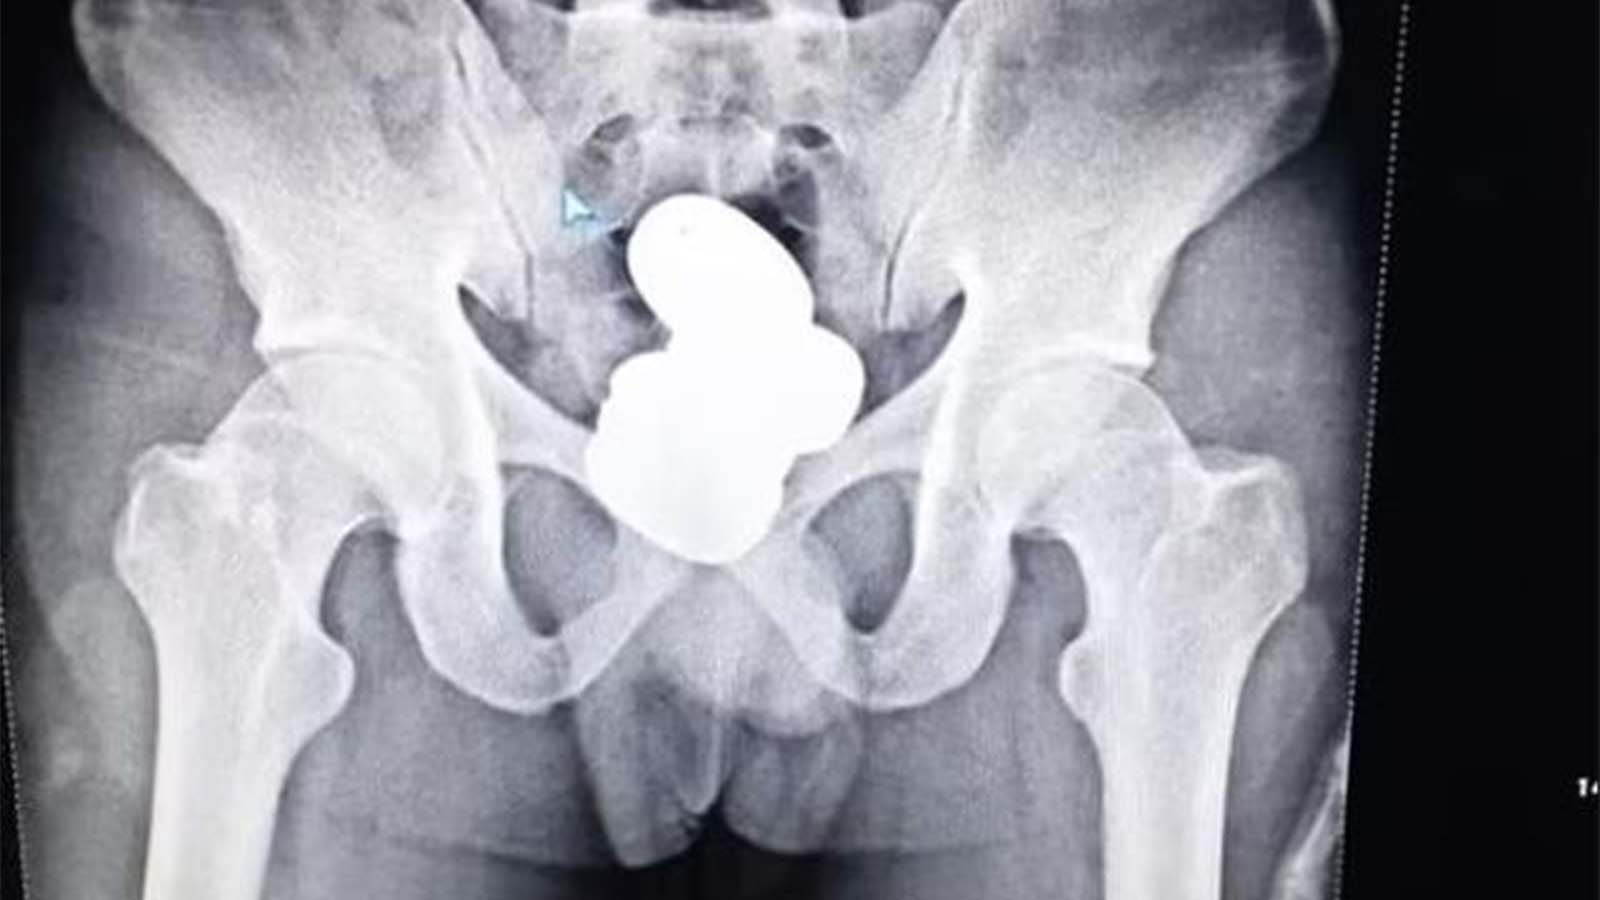

Güvenlik güçleri tarafından gözaltına alınan Mohammad Sharif isimli şahsın makatında dört kapsül haline getirilmiş 850 gram ağırlığında toz altın bulundu.